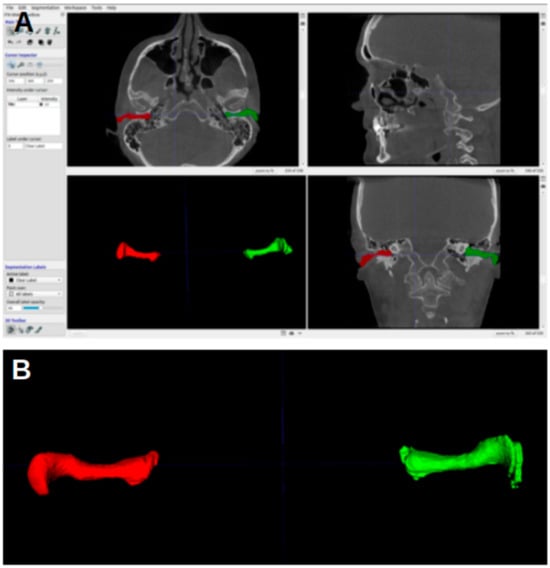

Figure 3 shows the ITK-SNAP window with segmentation, with the axial view shown in the upper-left image. In the first four landmarks, the crosshairs were placed such that they fell inside the segmentation of the acoustic meatus.

Figure 3. ITK-SNAP window. (A) Axial view. (B) Sagittal view. (C) Three-dimensional rendering of acoustic meatus. (D) Coronal view.